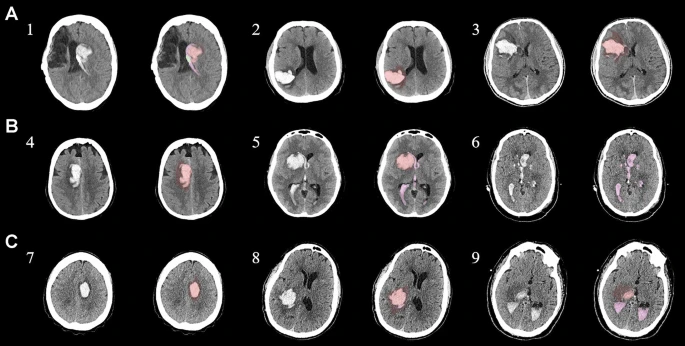

本研究納入2018年1月1日至2020年10月31日發(fā)病168小時內(nèi)發(fā)生急性ICH的患者。間充質(zhì)干細胞被靜脈注射給9名患者(5名女性,4名男性),平均年齡(范圍)為61(36-84)歲。表1總結(jié)了人口統(tǒng)計學和臨床??特征 。出于描述目的,患者按照入組順序獲得編號,并連續(xù)分配到三組中的一組,每組三人。根據(jù)模型 2 分割,ICH體積范圍為0.1至54.9mL(平均ICH體積為23.5mL)。5例ICH累及局部腦葉,其余則位于基底節(jié)或外囊深處。在三名患者中,ICH位于丘腦(圖1),在一名患者中,血腫位于多個腦結(jié)構(gòu)(即尾狀核、殼核和蒼白球)。平均而言,MSC在ICH后3天進行注射。

具有臨床特征的探索性成像體積模型分析

ABC/2模型1和模型2分割方法通過ICH和IVH體積的線性回歸顯示出良好的相關(guān)性(圖3a、b)。與模型2分割體積方法(例如,每個CT15-20分鐘)相比,模型1ABC/2派生的半定量方法和改進的Graeb IVH方法完成時間較短(例如,2-5分鐘)。有趣的是,NIHSS評分與IVH體積M2方法的比較顯示出線性相關(guān)性(R 2 ?= 0.7217),并且當IVH小于20mL或大于20mL時,NIHSS評分似乎出現(xiàn)聚類(圖3c)。PHE分析顯示MSC注射劑量和PHE體積之間存在輕微的負相關(guān)關(guān)系。

a,通過模型1ABC/2派生方法與vol模型 2(分割)進行的神經(jīng)影像ICH vol的線性回歸。b、IVH通過模型1和定量分割模型2方法對Graeb進行了修改。c,出血量和NIHSS評分與IVH量通過分割進行比較。